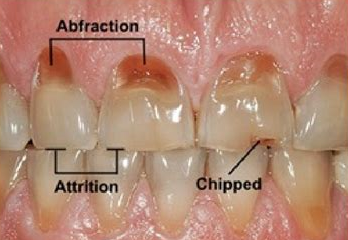

Dental damage associated with bruxism

Abfraction lesions

Abfraction refers to wedge-shaped defects near the gumline caused by biomechanical stress from clenching/grinding. These areas can become sensitive and may trap food debris, increasing decay risk. noordinarydentistry.com

Protective management (splints, occlusal adjustment) can slow progression and reduce discomfort.